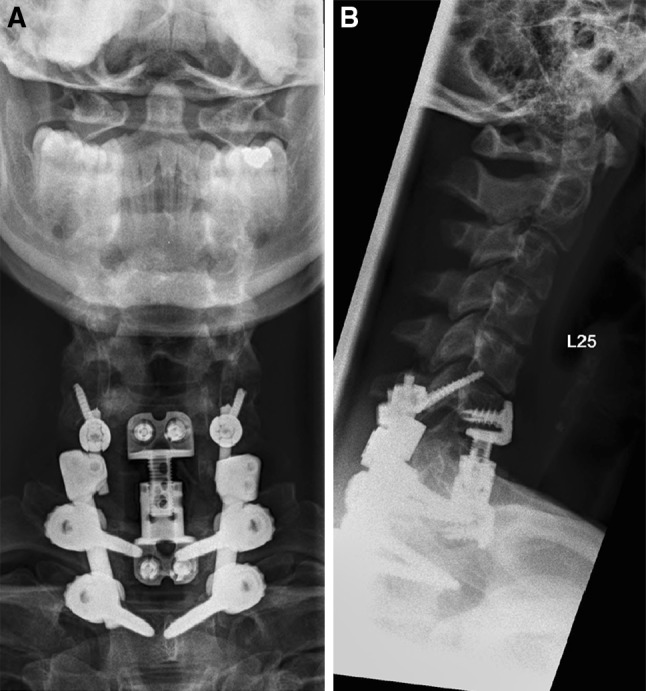

The later course was uneventful. 6 months postoperatively, a CT scan showed solid fusion of the fracture (Fig. 6). Hence, implant removal of the C0–C3 construct and of the C5 screws (shortening of the C5–T2 construct) was performed. Intraoperatively, no signs of fusion in the upper cervical spine could be detected and segments were still mobile. In the following months, patient underwent physiotherapy to regain as much as mobility of the cervical spine as possible. At the last follow-up, 12 months after implant removal, the patient was satisfied with the clinical result and did not complain about pain in the upper cervical spine. Due to the fusion from T6 to Th2, the overall cervical range of motion was somewhat restricted. On clinical examination, extension of the neck was still not possible and the cervical spine showed a kyphotic posture. The range of motion of the cervical spine was as follows: extension–flexion 0–0–30°, side-bending right–left 15–0–15°, rotation right–left 45–0–40°. A final CT scan showed stable radiological situation without loss of reduction or signs of pseudarthrosis. However, the cervical spine showed a global kyphotic alignment due to degeneration of the segments C2–C5. Adjacent segment degeneration was obvious at the segment C5/6 (Fig. 7).

Fig. 6.

CT scan before implant removal shows a consolidated fracture and centralized C2

Fig. 7.

X-ray control 12 months after implant removal